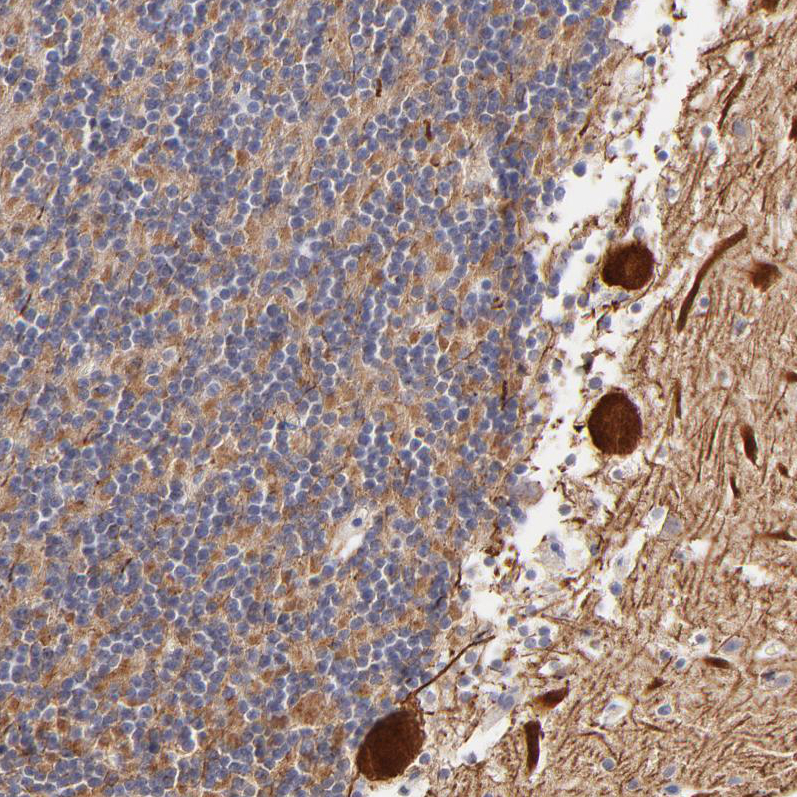

Immunohistochemical staining of human cerebellum shows strong cytoplasmic positivity in Purkinje cells.